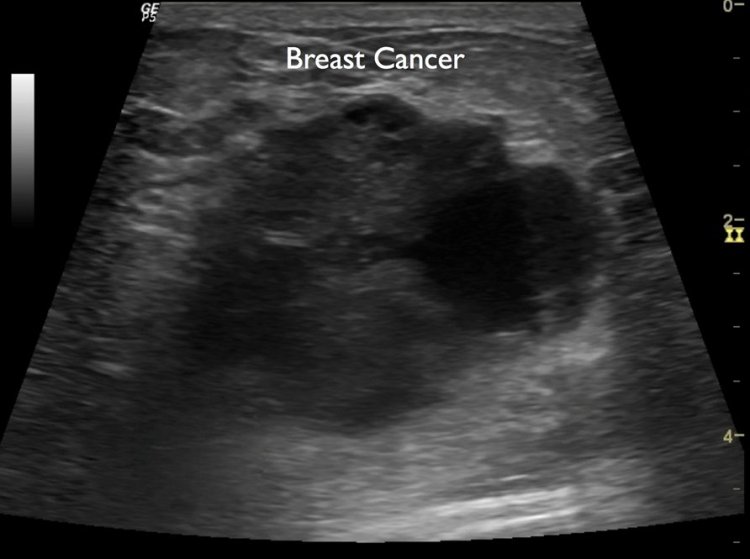

¿Qué tan rápido se propaga el cáncer de mama?

Frontiers - Prognostic and Predictive Value of the American Joint ...Publicado el 9 de marzo de ¿Qué tan rápido se propaga el cáncer de mama?:El cáncer es una enfermedad que se puede propagar rápidamente. El cáncer más común que se propaga rápidamente es el cáncer de mama. El cáncer de mama se propaga rápidamente porque comienza en un seno, luego se mueve al otro y luego a otras partes del cuerpo. Esto puede suceder en el lapso de unos pocos años.

Bueno, aquí estamos discutiendo "Qué tan rápido se propaga el cáncer de mama" para que las personas que esperan descubrirlo en detalle puedan familiarizarse con él y recibir tratamiento para detener su pronóstico. ¡Empecemos! ¿Qué tan rápido se propaga el cáncer de mama? Las personas a menudo preguntan sobre la tasa de crecimiento del cáncer de mama para ayudarlas a comprender el período de tiempo que tienen antes de buscar tratamiento. El crecimiento del cáncer de mama puede variar, pero algunos estudios indican que ha aumentado en los últimos años. Además, el cáncer de mama puede tener lugar por mutaciones genéticas, que podrían haber comenzado décadas antes de que aparezca clínicamente. Este tumor está formado por varias células que también se multiplican y dividen. Este proceso hace que el tamaño de un tumor aumente rápidamente. Aunque las células cancerosas generalmente se dividen al mismo tiempo, algunas forman tumores y otras no, y esto determina la tasa de cambio en el crecimiento. En comparación con otros tipos de cáncer, el cáncer de mama tiene una "fracción de crecimiento bajo", lo que significa que una proporción menor de células son cancerosas que otras. Las células de cáncer de mama crecen por división celular, pero pueden ser impredecibles porque a menudo están mutadas. En el Centro de Investigación del Cáncer Robert W. Franz en el Centro Médico Providence Portland, se descubrió que las células cancerosas solo pueden detectarse en promedio cada 30 días mediante un examen físico. Toma alrededor de 1 a 2 meses para que el crecimiento de un tumor se vuelva perceptible, por lo que incluso si una persona ha estado experimentando síntomas de cáncer desde hace 2 años, no es necesario mirar más atrás. El tiempo aproximado durante el cual el tumor estuvo creciendo es de alrededor de 2 a 5 años. Si bien es cierto que, en términos generales, las células se dividen para generar masa, los tumores no siempre crecen y se diseminan según la cantidad de células que tengan. El tamaño del tumor determina la probabilidad de que el tumor invada los tejidos cercanos, el sistema linfático o el sistema circulatorio y se propague. Sin embargo, la clasificación y clasificación del cáncer de mama es un proceso estándar para que los médicos traten o investiguen el cáncer de mama. Algunos estudios han encontrado que estos factores también están relacionados con las tasas de crecimiento del cáncer de mama: niveles hormonales, antecedentes familiares y edad. El cáncer de mama inflamatorio es de "crecimiento rápido", mientras que otros tipos de cáncer de mama tienden a ser de crecimiento lento. El cáncer de mama es muy común en las mujeres a medida que envejecen, pero generalmente encontramos que las mujeres jóvenes tienen cánceres de mama de crecimiento más rápido. Estos cánceres también tienden a ser más agresivos con grados tumorales más altos. Los cánceres triple negativos crecen más rápidamente que los tumores con receptores de estrógeno positivos. El tumor triple positivo también crece más rápido. Hay un aumento en el crecimiento del tumor de mama durante y después de la menopausia. Es probable que sea causado por la disminución de estrógeno durante este tiempo. Las mujeres que usaron terapia de reemplazo hormonal (TRH) después de la menopausia tuvieron, en general, una tasa de crecimiento de tumores de mama más rápida. Un grado más alto del tumor indica un tiempo de duplicación más rápido, según lo determinado por dos conjuntos de mediciones. El índice de marcadores tumorales, también conocido como índice Ki-67, o tiempo de duplicación, mide la rapidez con la que el tumor aumenta en una persona. Tenga en cuenta que estas son dos tecnologías diferentes y deben usarse juntas. Beneath the Surface: A Guide to Breast Imaging - Breast360.org - The American Society of Breast ... Aquí hemos discutido ciertos aspectos relacionados con el cáncer de mama y esperamos que ahora sepas cómo se propaga. Bueno, si tiene un síntoma de cáncer de mama y desea ponerse en contacto con el médico, visite Jaipur y programe una cita con la Dra. Tara Chand Gupta.